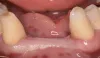

Фото 12: Место операции (зуб 2.5) через 6 месяцев после заживления.